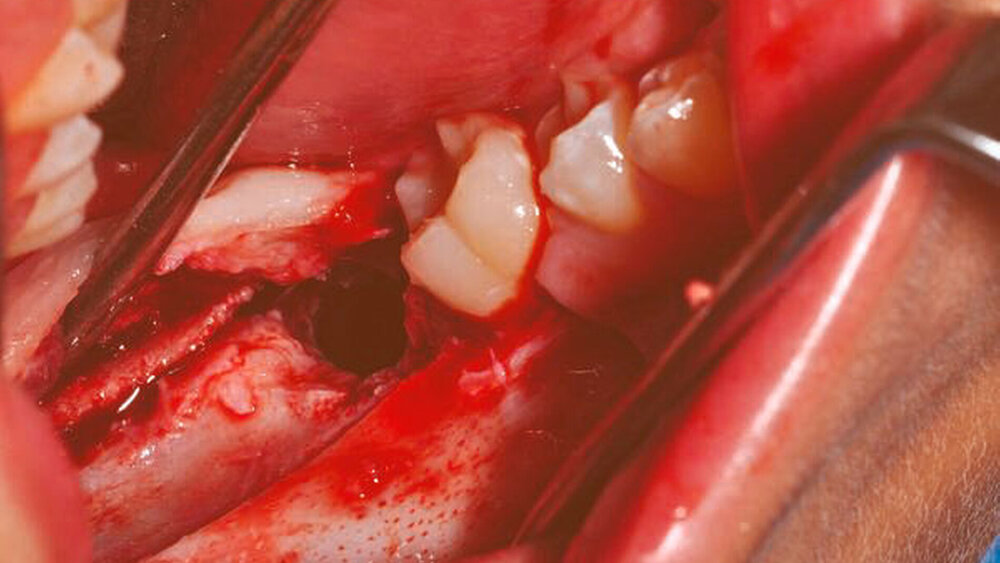

Unter der Verdachtsdiagnose einer follikulären Zyste wurde der Patient der operativen Therapie unter Intubationsnarkose zugeführt. Nach marginaler Schnittführung und distaler Entlastung entlang des aufsteigenden Astes des rechten Unterkiefers erfolgte die Anlage eines Knochendeckels mittels Piezochirurgie (Abbildung 3). Die Zyste wurde zusammen mit den retinierten Zähnen in toto exstirpiert (Abbildung 4) und zur histopathologischen Diagnostik versandt. Der Nervus alveolaris inferior am Boden der entstandenen Kavität (Abbildung 5) wurde vorher vorsichtig vom Zystenbalg entfernt. Anschließend wurde der Defekt mit Kollagen und autologem Knochen aufgefüllt. In der histopathologischen Aufbereitung zeigte sich ein durch flaches, mehrschichtiges Epithel ausgekleidetes fibrotisches Bindegewebe. Die Zystenwandung war fokal verdickt sowie äußerst zellreich mit monomorphen, unreif wirkenden Zellkernen. Die immunhistochemischen Analysen beschrieben eine zytoplasmatisch positive Färbereaktion auf CK-MNF und CK-Oscar. Der Proliferationsindex mit Ki-67 wies zwei bis fünf Prozent nukleär positive Zellen auf. Bei Chromogranin, S100 und Synaptophysin fand keine positive Färbereaktion statt. Somit konnte die Diagnose eines adenomatoiden odontogenen Tumors getroffen werden. Bei postoperativ komplikationslosem Heilungsverlauf konnte der Patient nach einem dreitägigen stationären Aufenthalt in die ambulante Weiterbetreuung entlassen werden. Zur weiteren Verlaufskontrolle wurde ein halbjährliches Nachuntersuchungsintervall vereinbart.